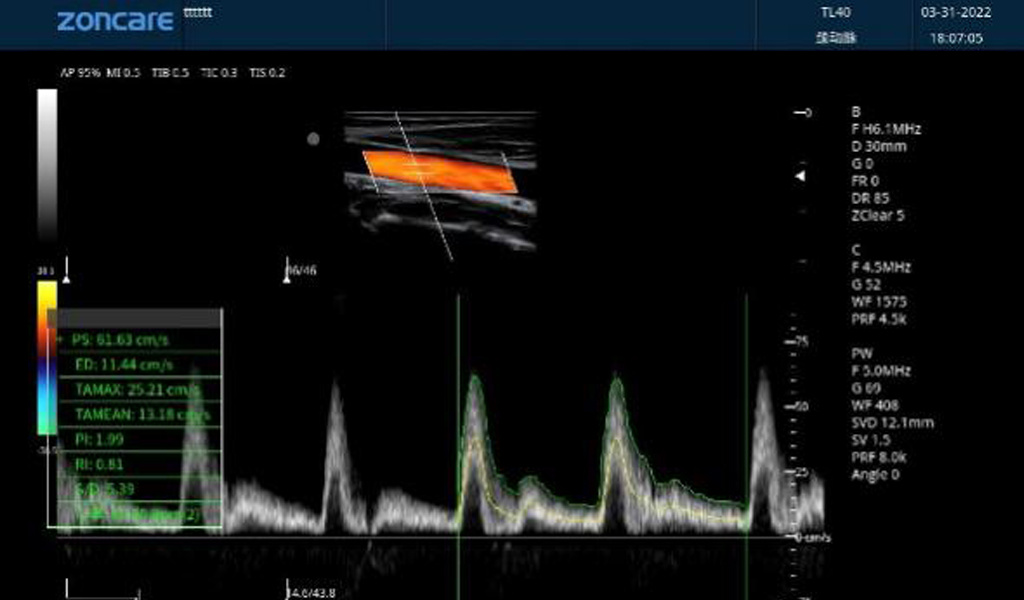

频谱自动包络测量